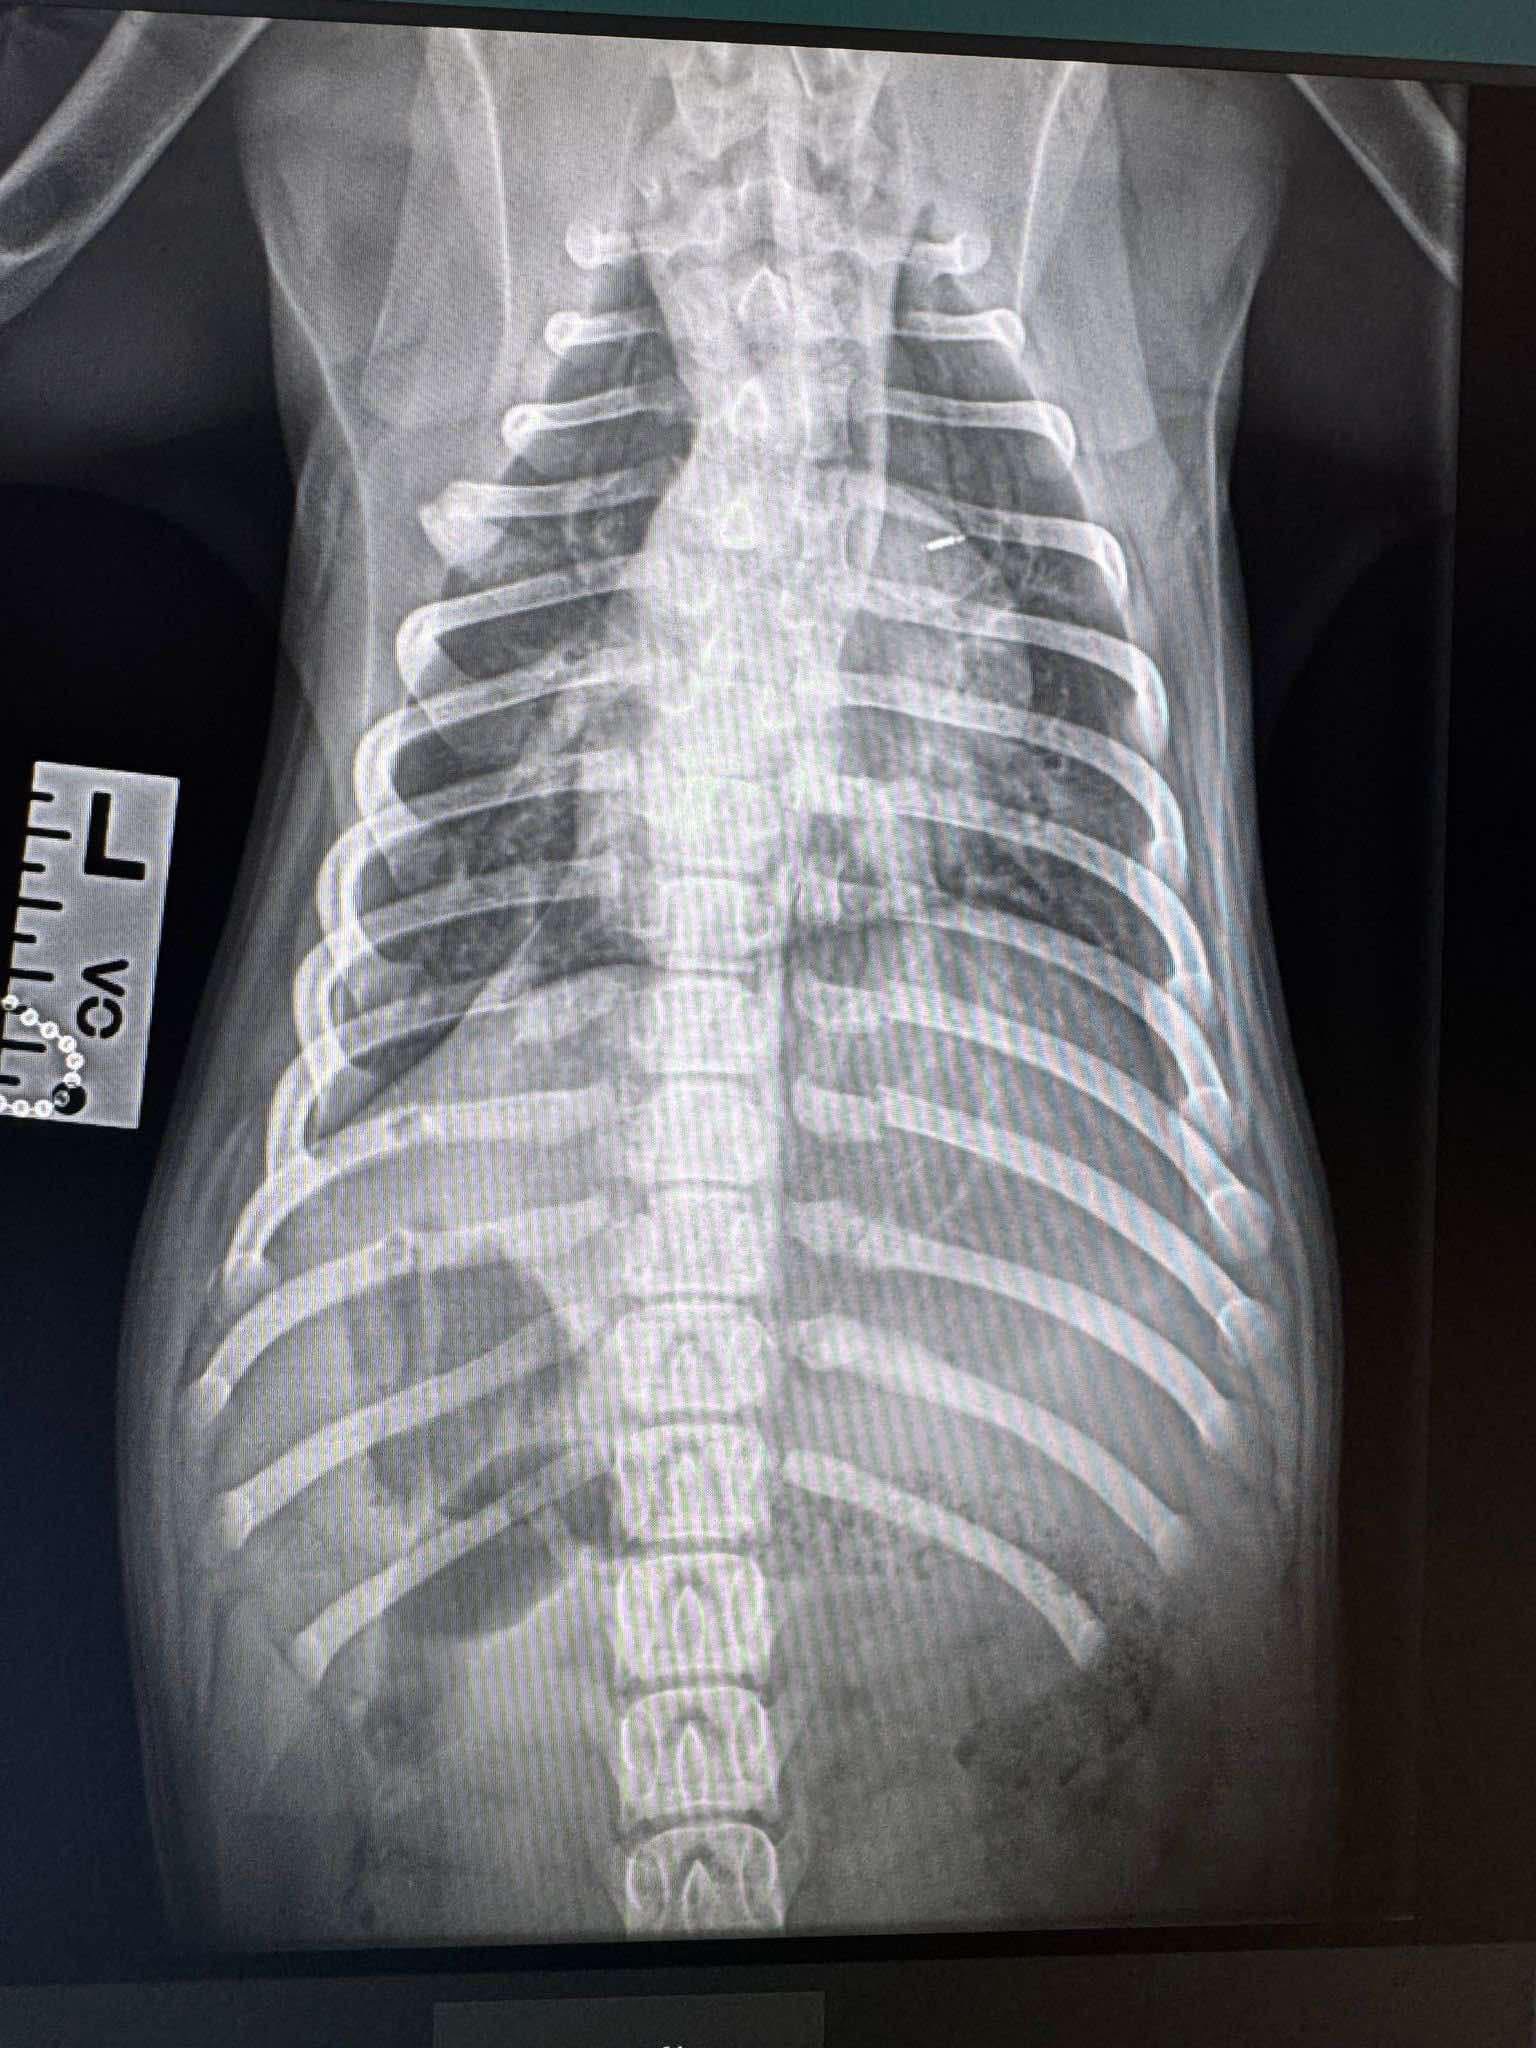

🔹 INJURIES TO LIL REDD

- 9 broken ribs close to her spine